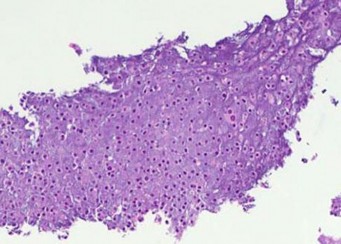

A 15-year-old male presents with deep knee pain awakening him at night. Radiographs show a permeative destructive lesion in the distal femoral metaphysis with a 'sunburst' periosteal reaction and Codman's triangle.

Biopsy confirms high-grade conventional osteosarcoma. What is the most critical prognostic factor for long-term overall survival in this patient?

Explanation

For localized high-grade osteosarcoma, the most important prognostic indicator is the histologic response to neoadjuvant chemotherapy. This is evaluated during the definitive resection. A 'good response' is typically defined as greater than 90% or 99% tumor necrosis. Patients who achieve this level of necrosis have a significantly improved disease-free and overall survival rate compared to 'poor responders' who have extensive viable tumor cells remaining.